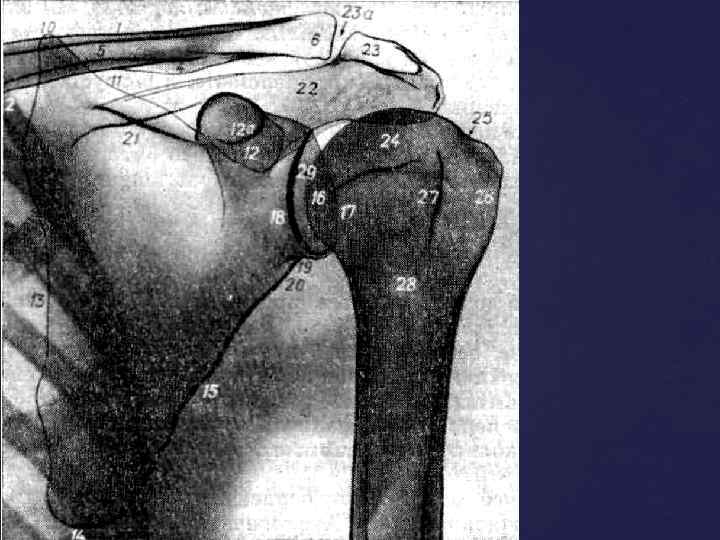

Головка плечевой кости в задней проэкции с вытянутой вдоль туловища конечностью, своей нижнемедиальной частью наслаивается на суставную впадину лопатки и проэцируется всегда выше нижней границы ее. Знание этой ретнгенологической нормы помогает распознать вывихи.

Головка плечевой кости в задней проэкции с вытянутой вдоль туловища конечностью, своей нижнемедиальной частью наслаивается на суставную впадину лопатки и проэцируется всегда выше нижней границы ее. Знание этой ретнгенологической нормы помогает распознать вывихи.

ПЛЕЧЕВОЙ СУСТАВ - появление двух т. о. в головке плечевой кости - 9 -12 мес - син-ие всех т. о в единую головку – 5 -8 лет - син-ие эпифиза и диафиза - 20 -23 года - появление множественных т. о. по краю суставной впадины лопатки – 4, 5 -5 лет - син-ие т. о. края суставной впадины – 67 лет

ПЛЕЧЕВОЙ СУСТАВ - появление двух т. о. в головке плечевой кости - 9 -12 мес - син-ие всех т. о в единую головку – 5 -8 лет - син-ие эпифиза и диафиза - 20 -23 года - появление множественных т. о. по краю суставной впадины лопатки – 4, 5 -5 лет - син-ие т. о. края суставной впадины – 67 лет